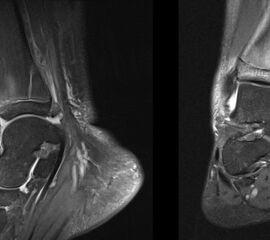

Osteochondrale Verletzungen

Osteochondrale Verletzungen können infolge eines Distorsionstraumas beobachtet werden (Taluskantenfraktur), teilweise lässt sich auch kein Trauma eruieren. Der es sich bei osteochondralen Verletzungen um keine Arthrose handelt, ist gerade bei Schmerzfreiheit ein defensives Vorgehen angezeigt. Bei offenen Wachstumsfugen kann eine osteochondrale Verletzung unter konservativer Therapie ausheilen.

Eine retrograde Anbohrung ist indiziert, wenn sich im MRT Verlauf eine zunehmende Sklerosierung im Randbereich der Läsion zeigt bei intakter Knorpeloberfläche.

Instabile Knorpelareale werden arthroskopisch entfernt in Verbindung mit einer Mikrofrakturierung der subchondralen Knochenlamelle.